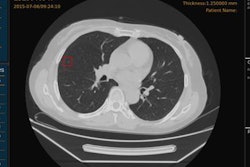

This year's competition focused on using machine learning to improve the accuracy of CT lung cancer screening. Participants used anonymized high-resolution lung CT scans from a publicly available dataset provided by the U.S. National Cancer Institute to create algorithms designed to determine when lesions in the lungs are cancerous, according to Booz Allen. The winners from among nearly 18,000 submissions are as follows: